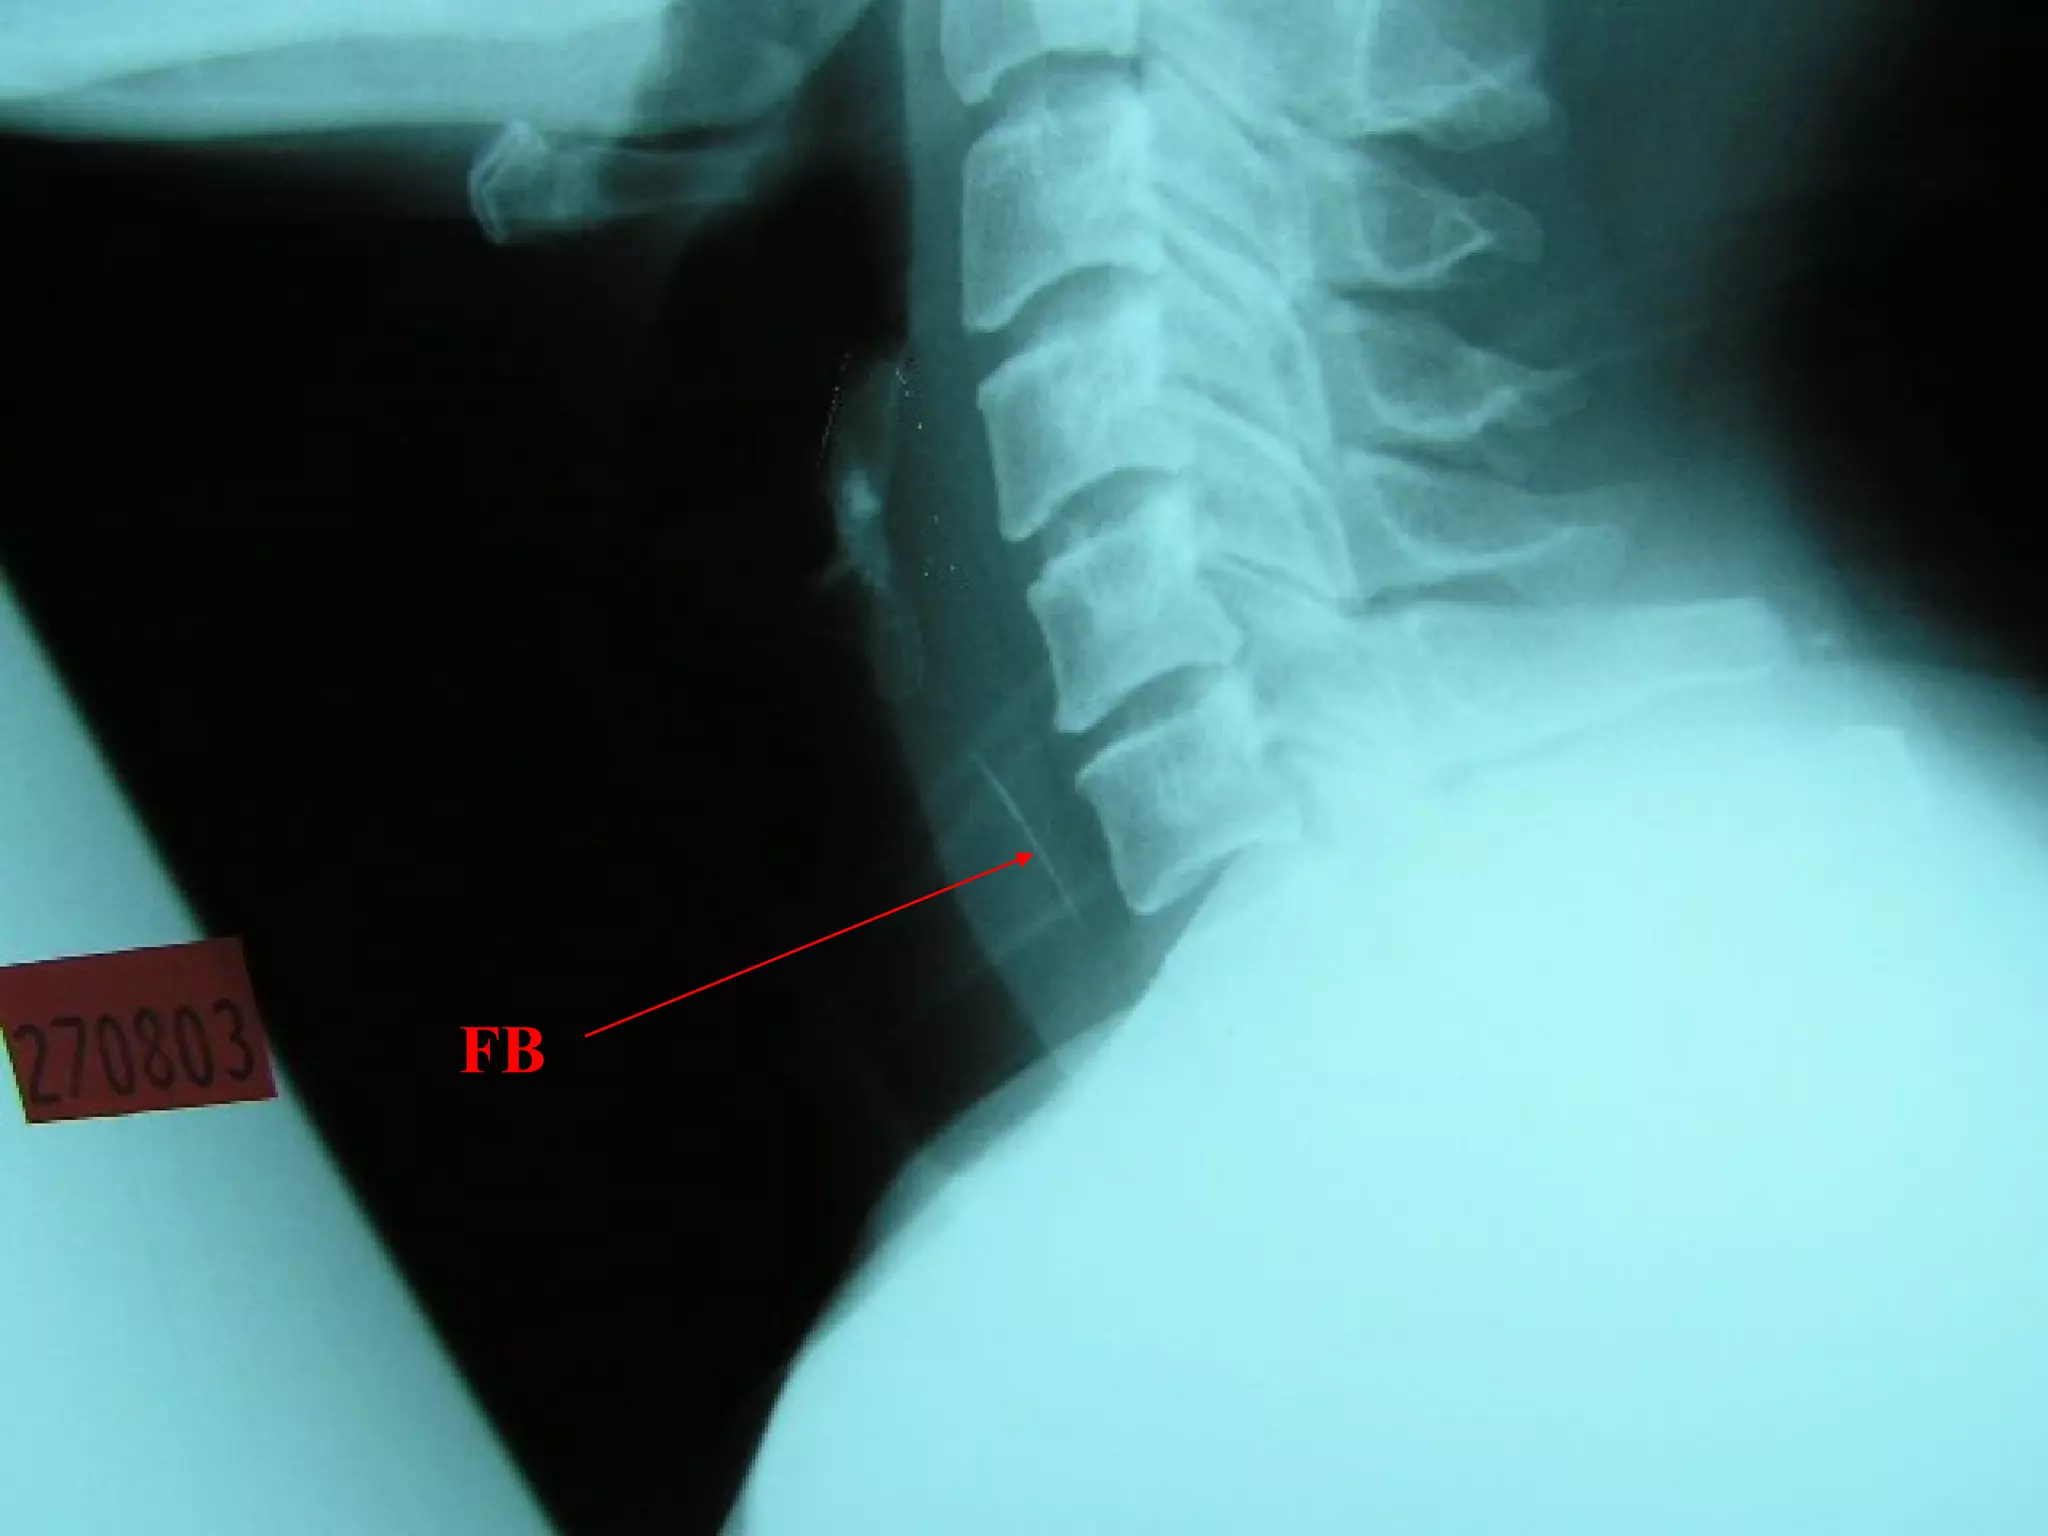

Lateral neck XR

FB